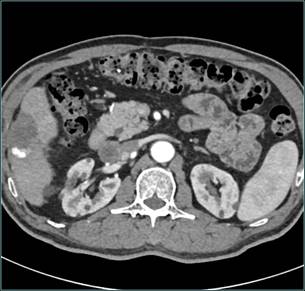

介入术后3月余复查CT(肿瘤明显缩小,失去血供):